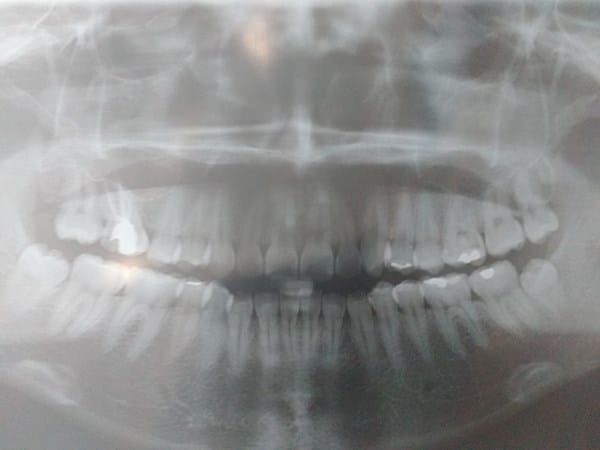

Tengo un dilema sobre que hacer en este momento. Tengo una muela con conducto partida la #27 y esta requiere una corona. Sin embargo, cuando me hice revisar me dijeron que era necesario que pensara en usar una corona temporal y realizarme una ortodoncia pues tengo un diente con mordida cruzada, la linea media un poco desviada y esto podría desgastarme los dientes. Mis dudas serían ¿en realidad necesito una ortodoncia o no es tan necesario y puedo dejar mis dientes como están? ¿Realmente puedo presentar problemas a futuro si decido no realizarme la ortodoncia? De antemano muchas gracias.

Adjunto fotos y una radiografía panorámica.